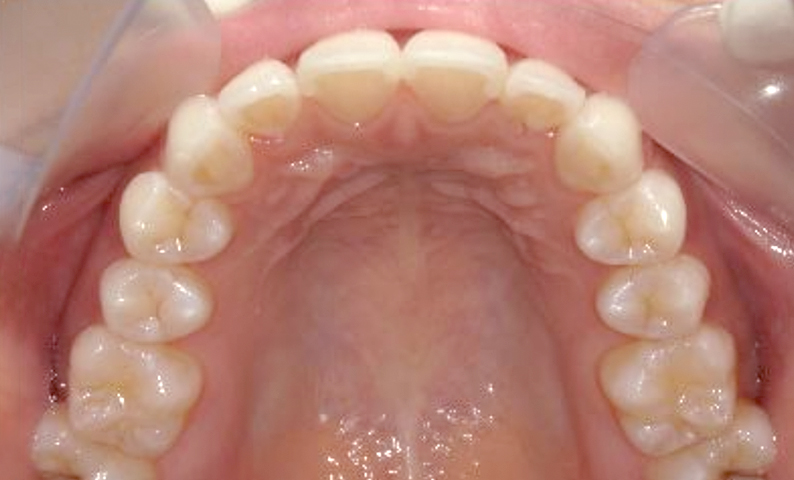

症例_001 前歯「捻転歯」症例

治療期間:6ヶ月金額:48万円+税20代女性少しのねじれ捻転歯下の八重歯

| Before | After |